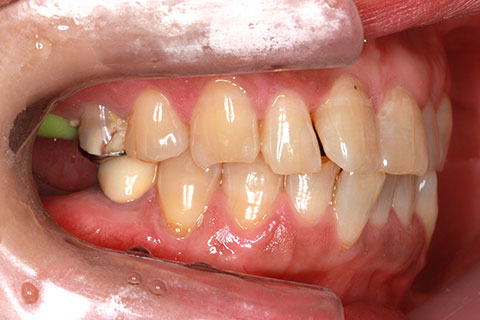

オールセラミックの症例2

- 年齢・性別

- 45歳男性

- 治療期間

- 2ヶ月

- 抜歯

- なし

- 治療費

- 70.4万円

- 備考

- 前歯8本の歯列不正によるセラミック治療

- 治療内容

- 歯質を削除し、セラミック冠をセメント合着

- 施術の副作用(リスク)

- 知覚過敏、歯髄炎、荷重負担